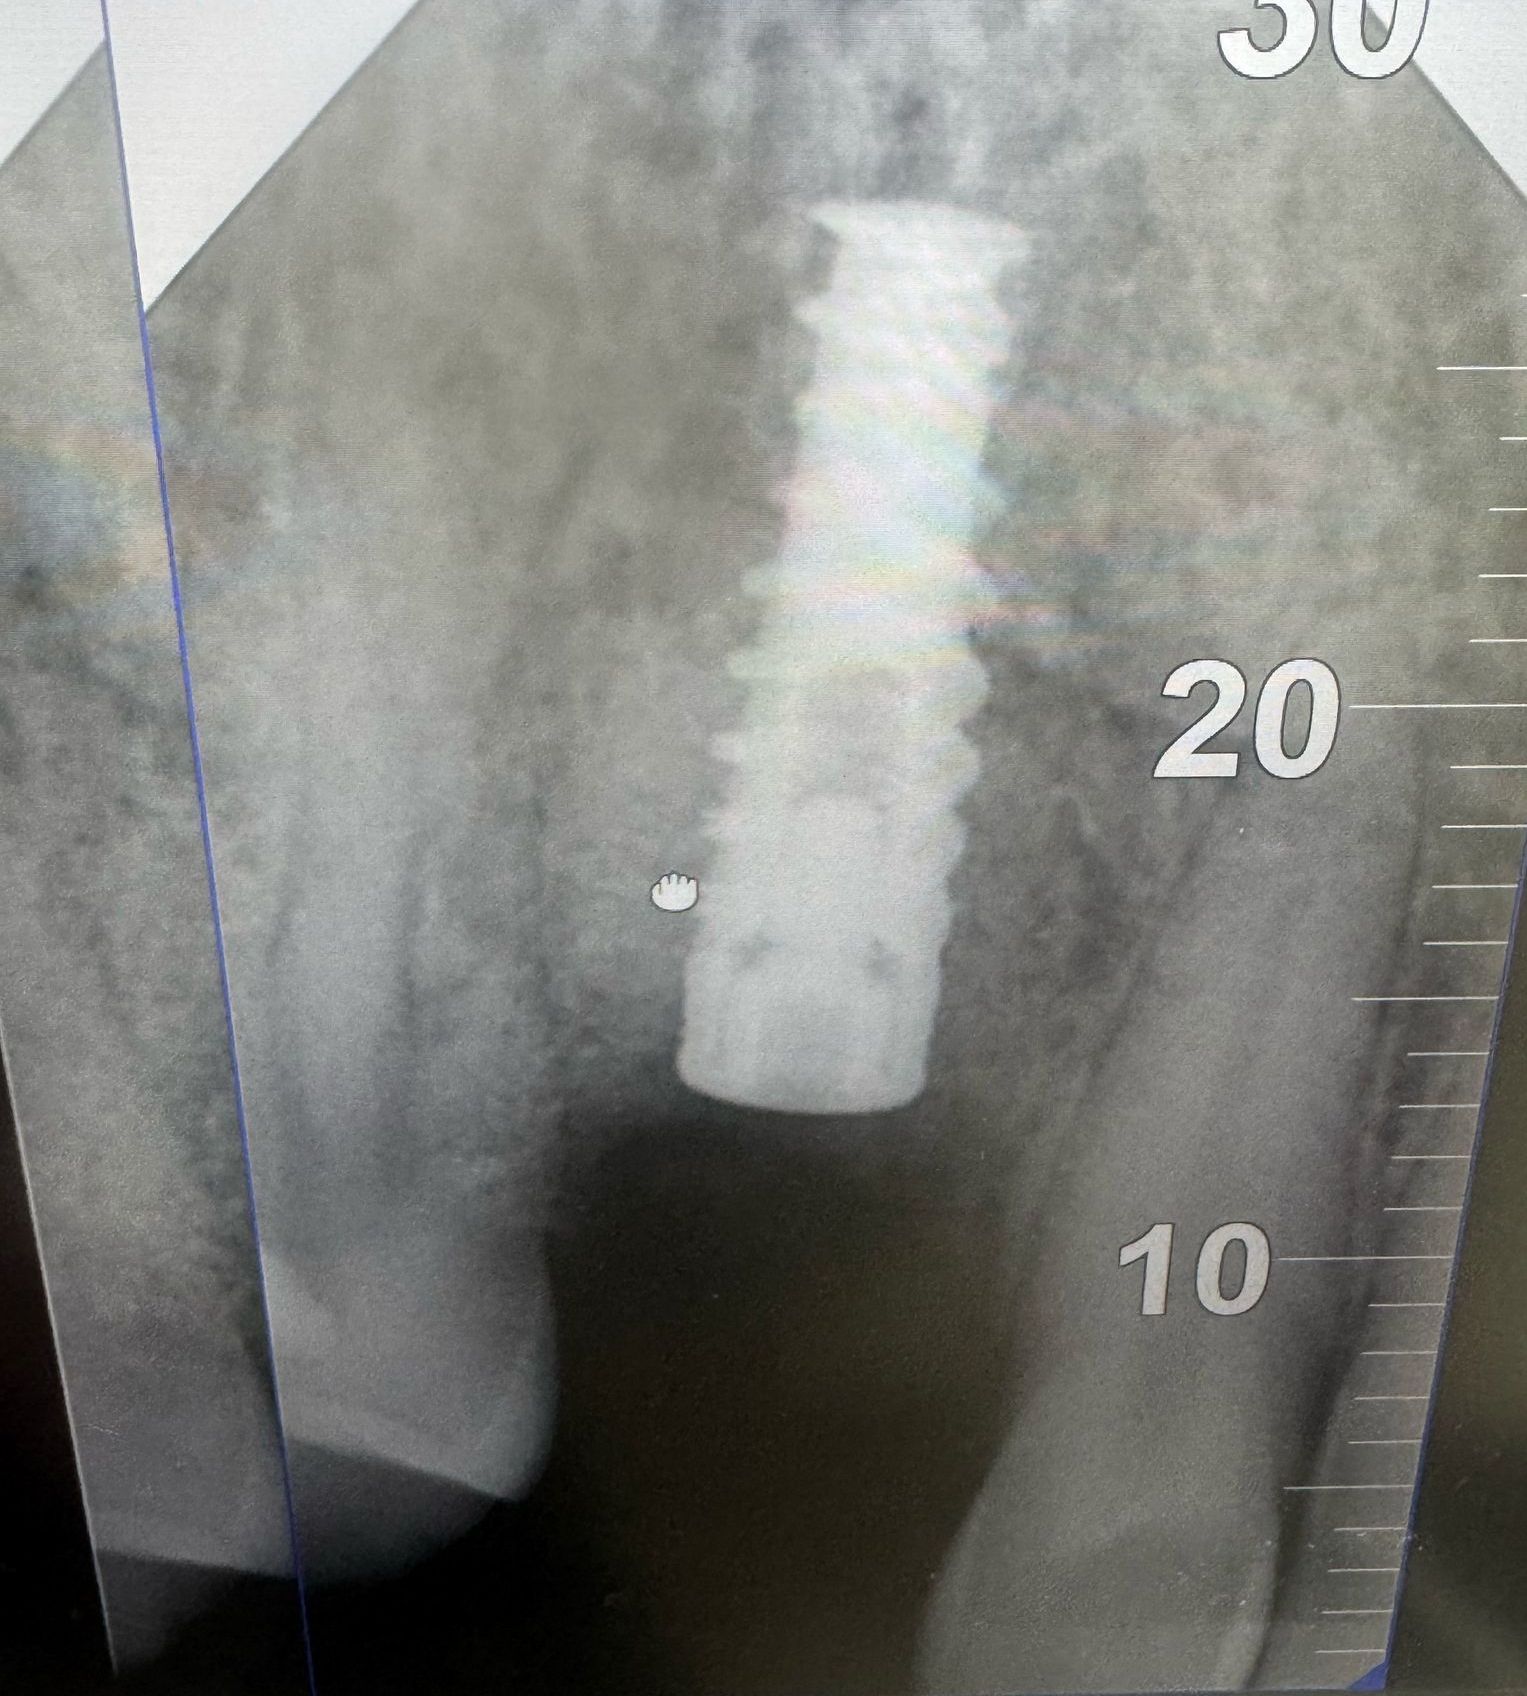

E' una procedura chirurgica che ha lo scopo di ricostruire (immagina 2) il volume osseo mancante e/o insufficiente (immagine 1), in alcune zone dell'osso alveolare dell'arcata dentale. Permette, dopo la rigenerativa dell'osso, di posizionare un impianto dentale (immagine 3) o di eliminare una tasca ossea adiacente ad un elemento dentale.